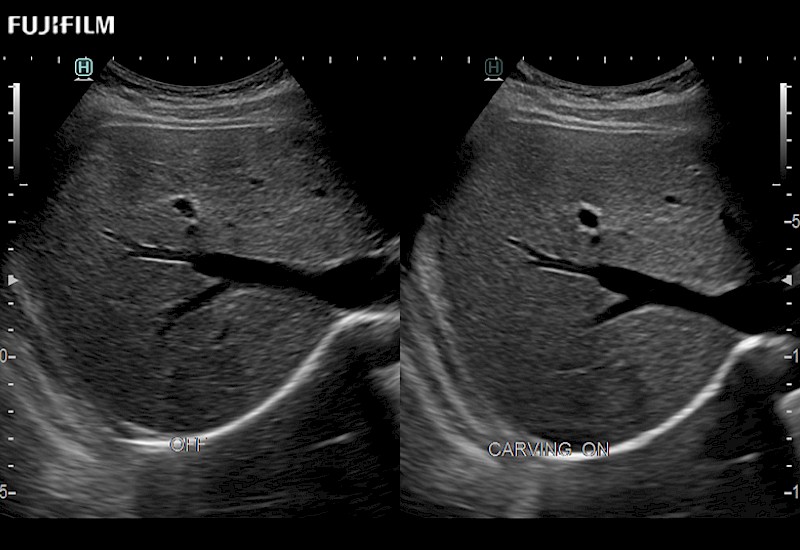

Our dedication to Laparoscopic Surgery allows us to offer superior image quality, outstanding system reliability and intuitive use of cutting edge technology.

The ARIETTA 750 incorporates all of the proven technologies and functions that medical professionals have come to expect from Fujifilm Healthcare.

ARIETTA 750 is the definitive diagnostic ultrasound solution for any clinical setting - Private Office, Imaging Center, or Hospital. The ARIETTA platform provides the ultimate in clinical performance with its state-of-the-art features and large user-friendly display.